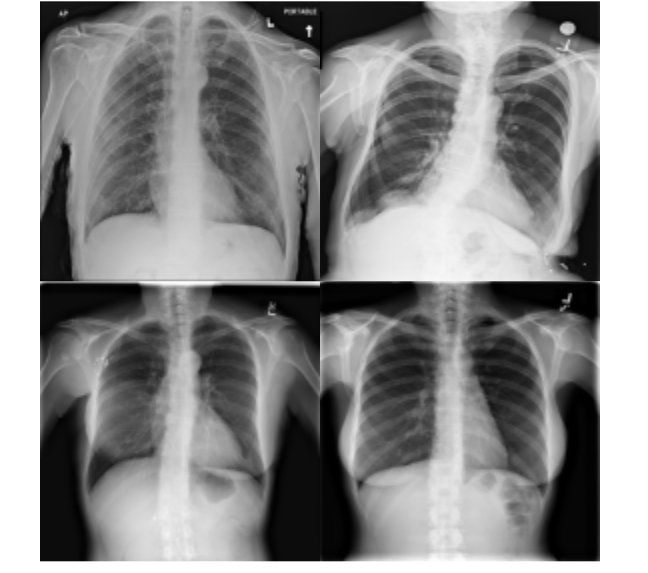

For the training of the proposed approach, we have investigated both positive and control group samples of the QaTa-COV19 dataset. By considering their overall qualities, we have manually annotated a set of samples and grouped them in two categories: poor quality samples {𝐲i}i=1Npsuperscriptsubscriptsubscript𝐲𝑖𝑖1subscript𝑁𝑝\{\mathbf{y}_{i}\}_{i=1}^{N_{p}} and high quality samples {𝐱j}j=1Nhsuperscriptsubscriptsubscript𝐱𝑗𝑗1subscript𝑁\{\mathbf{x}_{j}\}_{j=1}^{N_{h}}. Accordingly, we have labeled Np=2460subscript𝑁𝑝2460N_{p}=2460 poor quality and Nh=2094subscript𝑁2094N_{h}=2094 high quality samples. Samples from the dataset are provided in Fig. 5. Basically, assigning the training samples defines the transformation domains that is going to be learned by the R2C-GAN; therefore, it has a significant effect on the restoration performance. To avoid ambiguity in image domains, we have mainly excluded the mid-quality images in the formation of the training set. In the test phase, the restoration and classification performance evaluations have been performed by randomly selecting 19,2471924719,247 images from the QaTa-COV19 dataset. Overall, Table I presents the number of samples in the selected subset. As the test samples are randomly selected, the image quality varies in the test set, so it may contain poor, medium, and high quality images.

Refer to caption

(a)

(b)

Figure 5: Poor quality (a) and high quality (b) image samples from the QaTa-COV19 dataset.